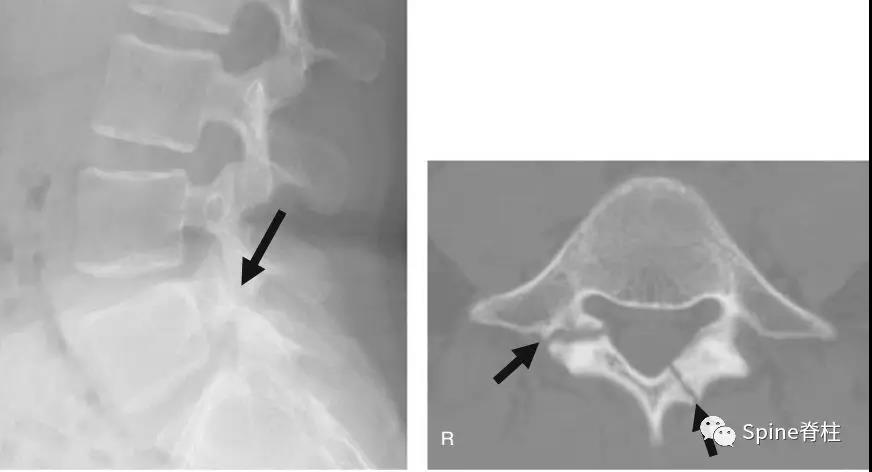

17岁芭蕾舞者,腰痛7个月

CT示:左侧为椎板裂(箭头),右侧为峡部裂(箭头)